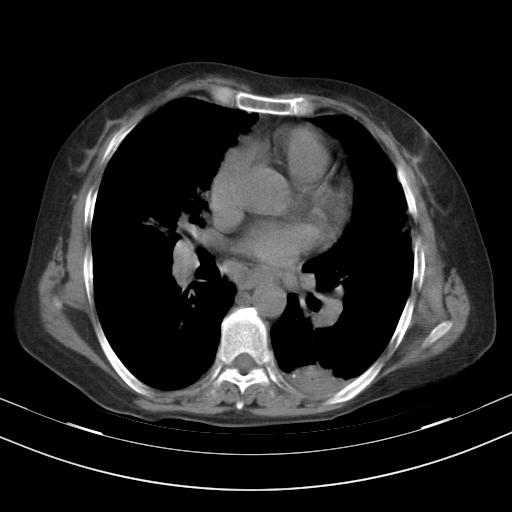

老年女性,嗜睡3天,意识模糊。轻咳,无发热。

1)两肺感染性病变;建议抗炎治疗后复查。2)纵隔淋巴结肿大。3)左侧胸腔积液。

3)左侧胸腔积液。